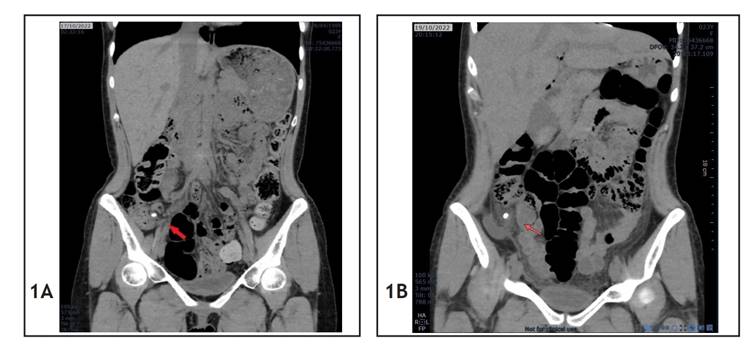

A 23-year-old woman was admitted to the emergency room of a public hospital in Lima, Peru, on October 17, 2022 (day 1), complaining of colicky pain in the right iliac fossa for four hours. Additionally, she reported a history of Cesarean section. Tests revealed her leukocyte count was 9,080/mm3; subsequently, she was diagnosed with acute appendicitis by clinical signs and symptoms, which was confirmed by computed tomography (CT) scan (Figure 1A). On the same day, a laparoscopic appendectomy was performed, where a 7 x 0.9 cm suppurative cecal appendix with approximately 50 cc purulent drainage in the pouch of Douglas was evidenced.

During the postoperative period, the patient made good progress and was discharged the day after the operation (day 2). On the second day of the postoperative period (day 3), the patient was readmitted to the emergency room of the same hospital because of pain in the hypogastrium, nausea and vomiting. A non-contrast CT scan showed the following findings (October 19) (Figure 1B): “impression of free fluid at the pouch of Douglas and presence of appendicolith.” Leukocytes: 6,020/mm3, C-reactive protein (CRP): 151.44 mg/l.

Figure 1 Case 1 CT scans. (A) Preoperative abdominal CT scan; the red arrow shows the appendicolith. (B) Postoperative abdominal CT scan; the red arrow shows the dropped appendicolith.